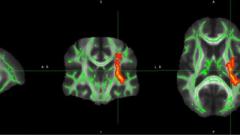

Neuropsychiatric symptoms emerged early in the COVID-19 pandemic as a key feature of the virus, with research confirming a range of neuropsychiatric manifestations linked to acute SARS-CoV-2 infection. However, the persistence of neurological symptoms in the post-acute and chronic phases remains unclear. This meta-analysis assesses the long-term neurological effects of COVID-19 in recovered patients, providing insights for mental health service planning.

The prevalence rates for the different symptoms were as follows: fatigue 43.3% (95% CI [36.1-50.9%]), memory disorders 27.8% (95% CI [20.1-37.1%]), cognitive impairment 27.1% (95% CI [20.4-34.9%]), sleep disorders 24.4% (95% CI [18.1-32.1%]), concentration impairment 23.8% (95% CI [17.2-31.9%]), headache 20.3% (95% CI [15-26.9%]), dizziness 16% (95% CI [9.5-25.7%]), stress 15.9% (95% CI [10.2-24%]), depression 14.0% (95% CI [10.1-19.2%]), anxiety 13.2% (95% CI [9.6-17.9%]), and migraine 13% (95% CI [2.2-49.8%]). Significant heterogeneity was observed across all symptoms. Meta-regression analysis showed higher stress, fatigue, and headache in females, and increased stress and concentration impairment with higher BMI.